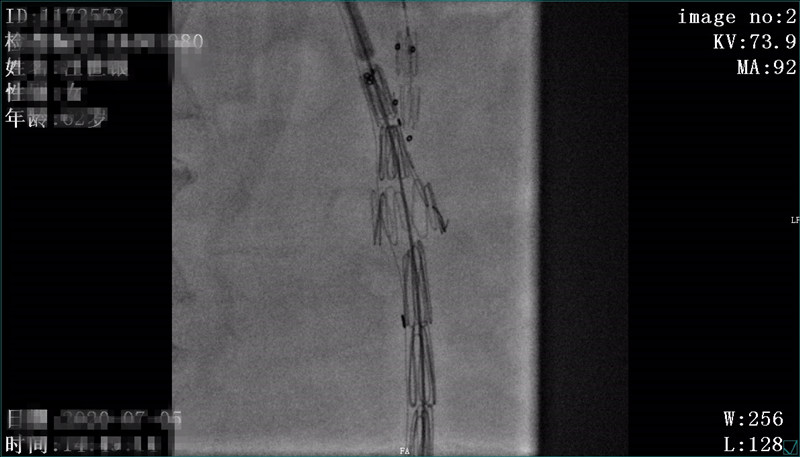

患者汪某,女,62岁,家住我县天堂寨镇,患者源于2年前无明显诱因下出现胸背部疼痛,外院检查后确诊"主动脉夹层",曾行"主动脉覆膜支架腔内隔绝术"。术后反复出现胸背部疼痛不适,伴有胸闷、咳嗽症状,休息后可好转。因上述症状加重就诊我院呼吸内科,门诊查主动脉全程增强CTA见主动脉弓边缘见一直径约11mm破口影,造影剂经破口流入主动脉周围血肿内。CTA提示:主动脉夹层,患者为求进一步诊治遂至介入科就诊,拟"主动脉夹层"收住入院。入院后我科积极完善相关术前准备及检查,于 7月5日在DSA下行“主动脉、双侧颈总动脉、左锁骨下动脉造影+分支型覆膜支架腔内隔绝术+左锁骨下动脉开窗覆膜支架植入术+胸主动脉覆膜支架植入术”。术后病情平稳,现患者胸闷症状消失、咳嗽明显好转。

术前CTA见造影剂经破口处外溢

术前造影,原支架近端可见造影剂外溢,原支架远端胸主动脉呈瘤样扩张

术中开窗后定位

术后造影,主动脉弓处破口消失,左颈总动脉显示可,左锁骨下动脉显示良好,胸主动脉显示良好,原扩张段消失,支架周围未见明显内漏。